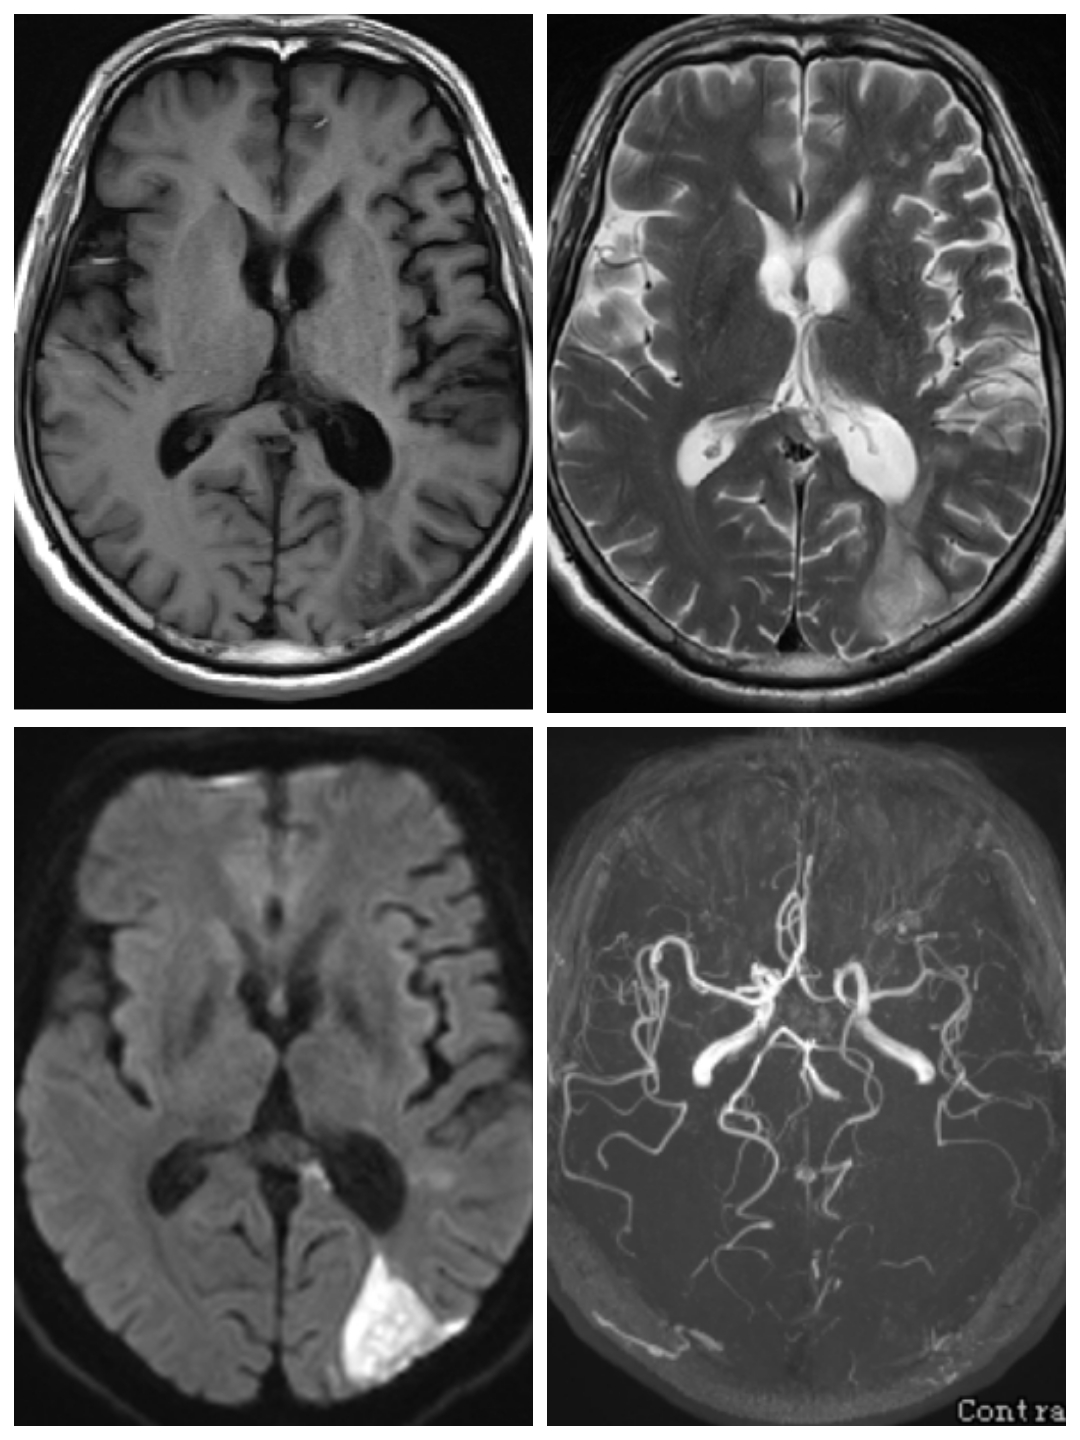

吴某某,56岁,女性,因“右侧眼睑下垂一周”入院

查体:神志清,右眼瞳孔4mm,对光反射消失,右眼睑下垂

DSA提示右侧后交通动脉瘤,左侧颈内动脉末端动脉瘤,左侧后交通圆锥,左侧海绵窦夹层动脉瘤。

下面这个动脉瘤像不像一颗爱心,可是它很“凶残”。随时可能破裂出血,危急患者生命。

我们术中先解决右侧后交通责任动脉瘤,再解决左侧颈内动脉末端以及海绵窦夹层动脉瘤,手术顺利,动脉瘤消失,可谓一箭三雕🐮!